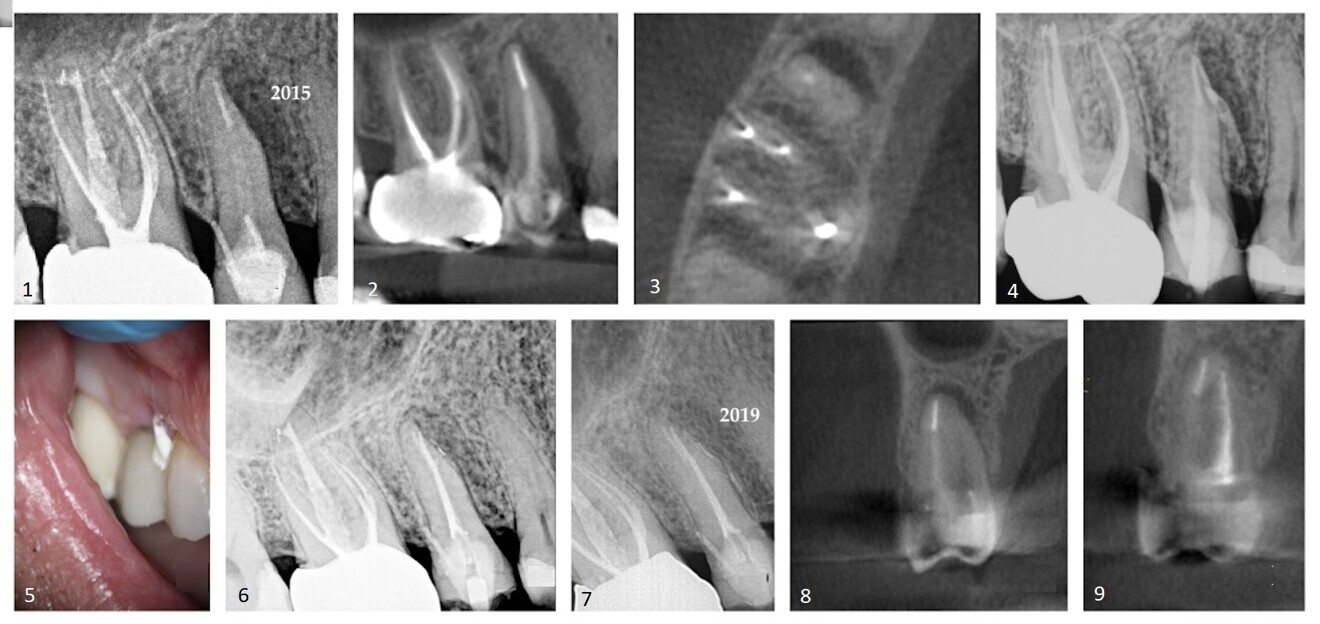

The patient provided a periapical radiograph showing a mesio-proximal periradicular radiolucency associated with tooth #15 (Fig. 1). The sagittal slice of the CBCT volume (Carestream CS 9000, Carestream Dental) showed the extent of the lesion (Fig. 2). In the previous root canal therapy, only the buccal canal had been detected and treated. The axial slice showed an untreated palatal canal (Fig. 3). A fibre post placed in the buccal canal had been used to retain the core. The patient was advised of the misdirected anchoring pin extending into the periodontal ligament. With the patient’s consent, it was decided to selectively treat the palatal canal.

After an interim six-week period of calcium hydroxide therapy (UltraCal XS, Ultradent; Figs. 4 & 5),6 the root canal space was obturated using a warm vertical condensation technique.7 The obturation material was expressed into a lateral branching portal of exit (Fig. 6). The four-year follow-up showed resolution of the lateral lesion (Figs. 7–9). The initial presumption of a fractured root was proven false, suggesting that diagnosing conditions based on insufficient data acquisition is unreliable. The use of CBCT is an imperative in endodontic procedures of any kind provided ALARA (as low as reasonably achievable) principles regarding radiation dose are followed.

Case 1—Fig. 1: An area of periradicular rarefaction was evident along the mesio-proximal aspect of tooth #15. Previous root canal therapy and a pin-retained post and core supporting a zirconia crown were noted. Fig. 2: The sagittal slice of the CBCT volume showed the lateral lesion extending to the alveolar crest. Fig. 3: The axial slice of the CBCT volume showed the extent of the rarefaction adjacent to the mesial aspect of the root and the presence of an untreated palatal canal. Fig. 4: Selective treatment of the palatal canal was performed. Calcium hydroxide was inserted in the canal space. Fig. 5: The extrusion of the interim calcium hydroxide medicament through the sulcular area of tooth #15 was evident. Fig. 6: A lateral branch of the root canal space containing the obturation material exited into the interface of the middle and apical thirds of the root. Fig. 7: A periapical radiograph taken four years after treatment showed osseous regeneration and the reformation of the periodontal ligament. Fig. 8: The coronal slice of the CBCT volume showed the pre-op periradicular radiolucency. Fig. 9: The coronal slice of the CBCT volume taken four years after treatment showed the resolution of the periradicular radiolucency.